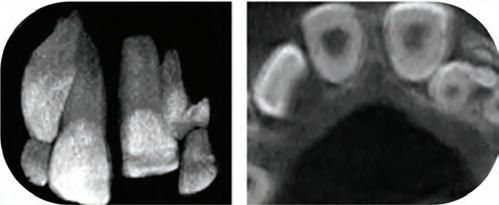

Fig. 1a: A panoramic reformatting of the CBCT scan, made by artificial intelligence, with automatic marking of the inferior alveolar nerve canal.)

Fig. 1b: A panoramic reformatting of the CBCT scan, performed by a human radiographer, with manual marking of the inferior alveolar nerve canal.)

Fig 2: Automatic measurement of the height and width of the alveolar ridge at the designated implantation site (Diagnocat, Diagnocat Inc., USA).

Figure 3a-c: 3D Imaging of the patient’s jaw and teeth. The volume of the CBCT imaging was segmented to STL models, and then the mandible model was made semitransparent to show the IAN canal pathway. (The 3D models were segmented with Diagnocat (Diagnocat Inc., USA) and displayed in the Exocad Webview software (available for free use at webview.dental).

R., a 40-year-old male, came to the dental clinic due to a previously extracted tooth #19 (ISO 36), and asked for an implant-supported crown to be placed. He was referred for a CBCT at an imaging center, and the resulting 3D volume was uploaded to an artificial intelligence system (Diagnocat, Diagnocat Inc., USA) to perform automatic slicing, detection of the inferior alveolar nerve, and alveolar ridge measurements. Parallel to that, a human radiographer in the imaging center created a manual cross-sections report, that was attached to the 3D DI-COM file.

In the panoramic reformatted image produced as part of the AI-based cross-sections report, it seemed that the pathway of the inferior alveolar nerve forms a loop towards the mandibular foramen, close to the future transplant site. (Fig. 1A) It is unfortunate to mention that a human interpreter

did not mark this loop, (Fig 1B) perhaps due to alternate positioning of the panoramic cross-section.

In light of this discrepancy, I ordered a rendering of the 3D volume to a digital STL model, in order to further appraise the distance between the mandibular foramen and the planned implant placement site. The cross-sectional measurements (Fig. 2) and the segmentation to a 3D model (Fig. 3) were carried out by the same artificial intelligence system (Diagnocat, Diagnocat Inc., USA). These made it possible to understand the exact location of the nerve, and to make sure that it was indeed out of range of danger in this case.